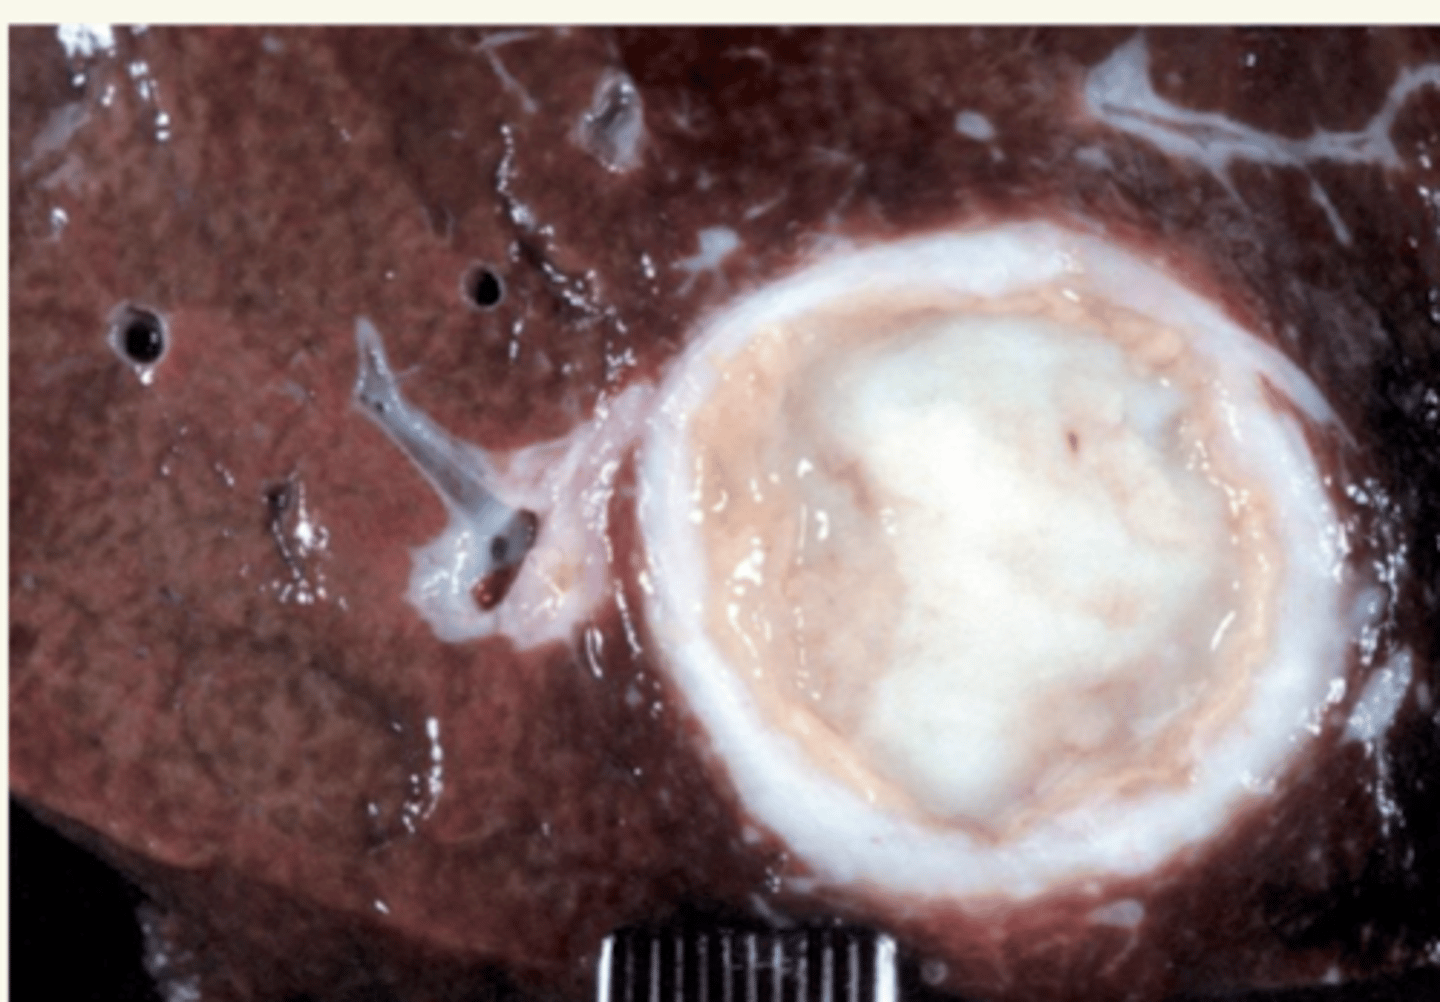

hepatitis purulenta, por bacteria

¿diagnóstico morfológico y etiológico?

(muchos neutrófilos)

hígado.

hepatitis purulenta

(con abscesos)

¿una infección del hígado por bacterias causará qué tipo de hepatitis?